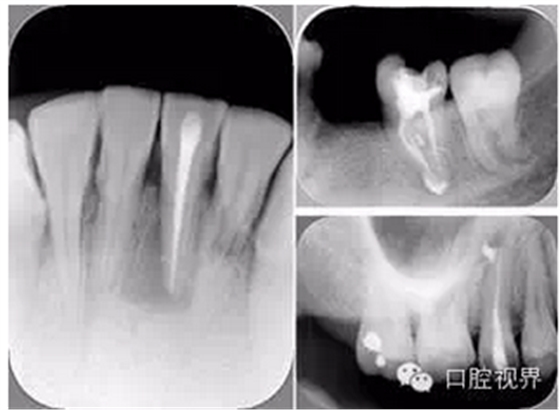

( 1 )術(shù)前:術(shù)前 X 線片用來了解牙齒的大概情況。術(shù)前預(yù)期為多根牙時 X 線片應(yīng)偏頭拍攝。

( 2 )診斷絲:根據(jù)術(shù)前 X 線片進行開髓、根管的初步預(yù)備后,需要插入診斷絲,用來指示工作器械位置。常用 10 號或 15 號擴大器作為診斷絲插入牙髓腔。

( 3 )主牙膠尖確認:通過術(shù)前預(yù)期和診斷絲診斷,明確工作長度、牙根走向,進行根管預(yù)備。之后應(yīng)進行主牙膠尖(中銼)確認,已明確根管是否適合充填。

( 4 )術(shù)后:觀察治療效果。

左圖為根管充填術(shù)后 X 線片。圖中可見,根管充填較好。右下圖有白色小點,為側(cè)方加壓導致糊劑擠出所致,表明根管充填比較致密。

多根牙時候需進行偏移投照,正位投照無法說明具體哪根牙根管充填效果。